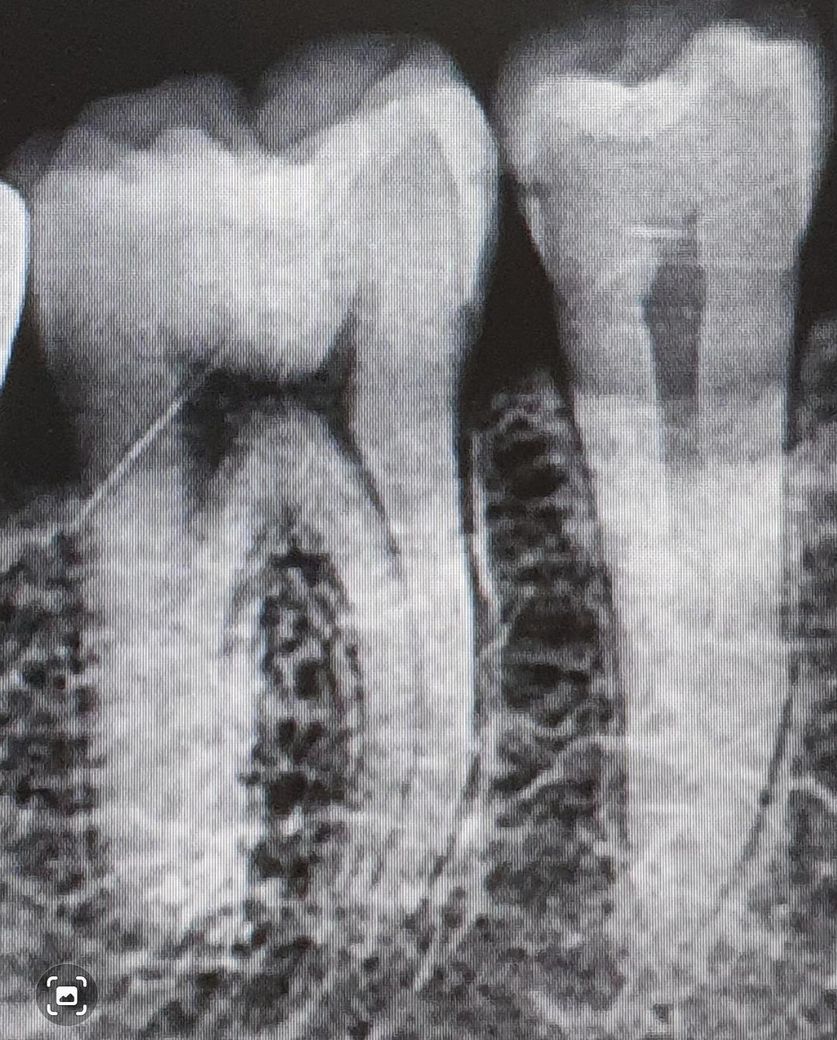

2017년 엑스레이

2025년 엑스레이 입니다.

충치가 안쪽으로 어느 정도 진행된 것으로 보입니다. 인레이 하는 것이 좋을 것으로 판단됩니다.

치료하시는게 좋습니다. 이미 임상사진으로 봐도 거뭇거뭇하게 보이고 방사선사진상으로도 충치가 안쪽까지 진행되어 정지될 우식이 아닙니다.

지금은 신경을 건드리지 않아서 괜찮을 수 있지만 신경이 건드려서 가만히 있어도 아프게된다면 신경치료 및 크라운 치료로 넘어갈 수 있으니 아직 그정도까지 썩지 않았을 때 치료 받으시길 바라겠습니다.

겉으로 보는 것보다는 안쪽 충치가 좀 있을 수도 있습니다. 신경이랑 거리가 얼마 안되는 옆면 충치이므로 미리 치료를 진행해도 좋을 것 같습니다.

오른쪽 아래 J 소구치의 경우에는 인접면에 충치가 있는 것으로 보입니다. 인접면에 충시가 있는 경우 보통 인레이라고 하는 간접 수복 치료를 통해서 치료를 하게 됩니다. 육안으로는 보이지 않지만 인접면에는 충치가 클 수 있기 때문에 치과에서 검사를 하시고 정확하게 치료를 하는 것이 좋을 것으로 생각됩니다.